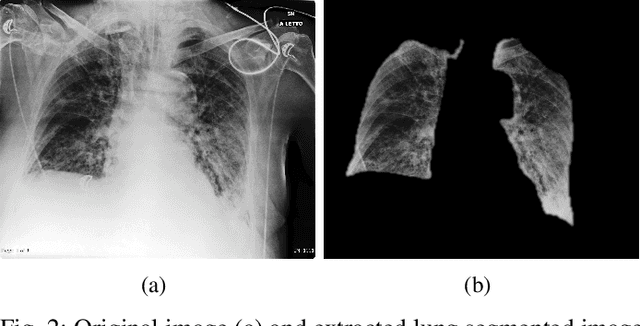

Abstract:The possibility to use widespread and simple chest X-ray (CXR) imaging for early screening of COVID-19 patients is attracting much interest from both the clinical and the AI community. In this study we provide insights and also raise warnings on what is reasonable to expect by applying deep-learning to COVID classification of CXR images. We provide a methodological guide and critical reading of an extensive set of statistical results that can be obtained using currently available datasets. In particular, we take the challenge posed by current small size COVID data and show how significant can be the bias introduced by transfer-learning using larger public non-COVID CXR datasets. We also contribute by providing results on a medium size COVID CXR dataset, just collected by one of the major emergency hospitals in Northern Italy during the peak of the COVID pandemic. These novel data allow us to contribute to validate the generalization capacity of preliminary results circulating in the scientific community. Our conclusions shed some light into the possibility to effectively discriminate COVID using CXR.